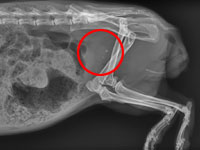

天竺鼠頻尿?『啄木鳥寵物醫學檢驗中心』曝:膀胱結石所害

一歲多的天竺鼠到動物醫院就診時,有頻尿、血尿,尿尿時還會吱吱叫…。『啄木鳥寵物檢驗中心』立刻展開檢查...